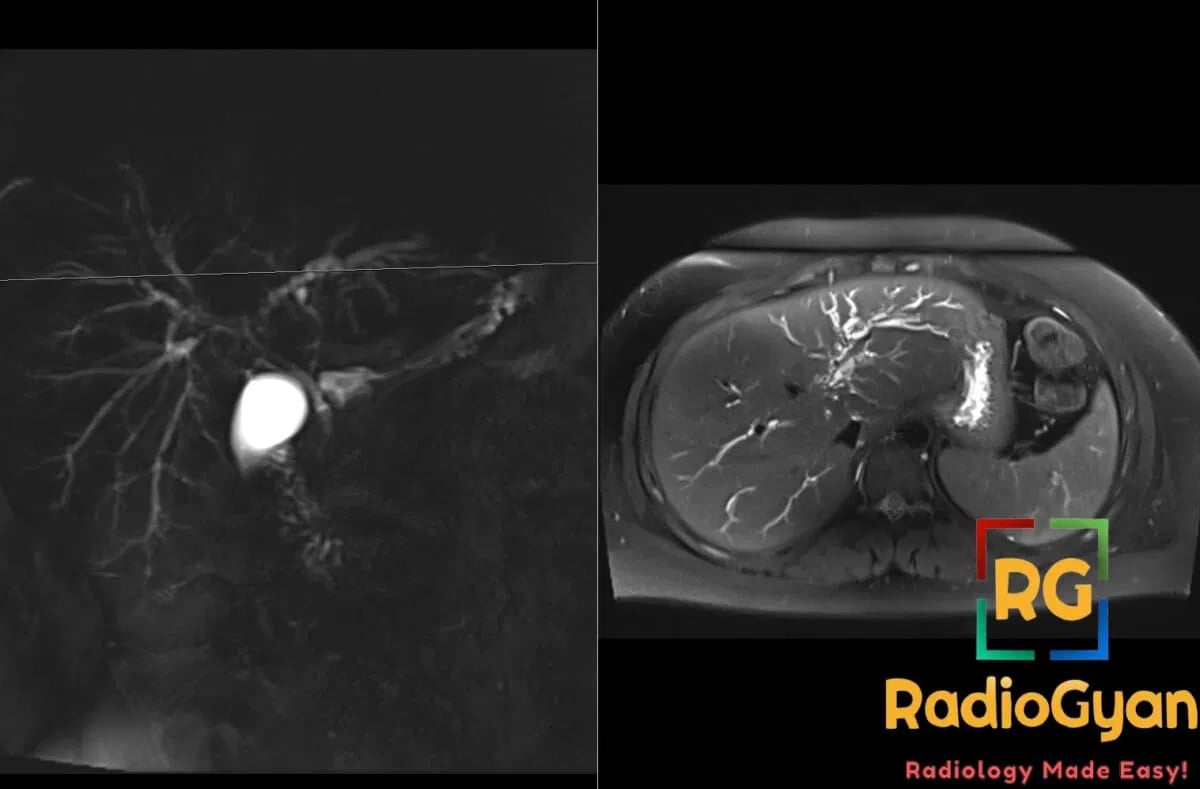

- MRI:ย MRCPย is diagnostic modality of choice; classicย “string of beads” signย with alternating strictures and dilatations;ย pruned tree appearanceย of intrahepatic ducts; T2 hyperintenseย periductal thickening;ย dominant stricturesย appear as severe focal narrowing

- Signs:ย String of beads signย – alternating strictures and dilatations on MRCP;ย pruned tree signย – loss of peripheral bile duct branching;ย periductal halo signย – T2 hyperintense rim around bile ducts